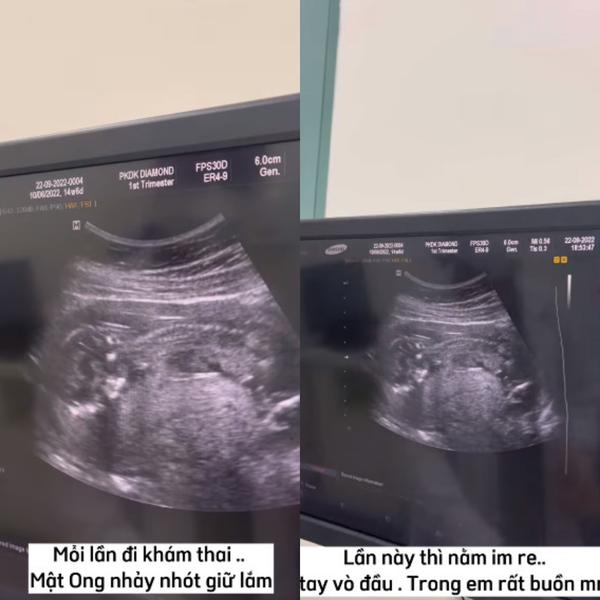

“Mỗi lần đi khám thai, Mật Ong (tên em bé trong bụng - PV) nhảy nhót dữ lắm. Lần này thì nằm im re, lấy tay vò đầu, trông rất buồn mọi người ạ.

Bác sĩ khuyên mẹ nên vui vẻ và ăn uống đầy đủ vì em bé hơi nhỏ. Nghe xong câu đó, em cảm thấy có lỗi vô cùng cả nhà ạ.